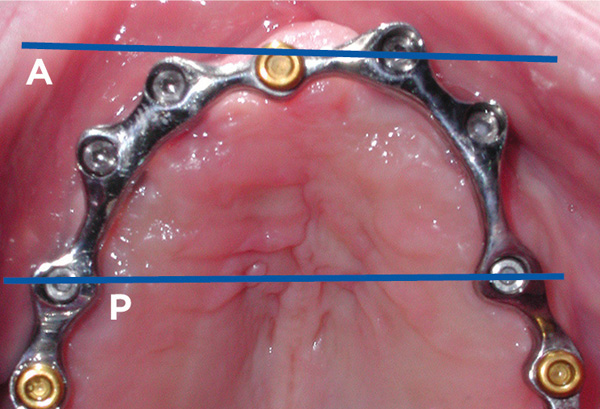

A-P ratio refers to the distance between the most anterior implant(s) (the A) and a line drawn between the most posterior implants (the P). The distance between the two lines is measured, and that determines how far posteriorly the prosthesis can be cantilevered. Accepted distance allows for 1 to 1.5 times the A-P ratio to be cantilevered distal to the most posterior implant.3,4 Patients with ovoid arch forms typically allow better A-P ratio due to the available positions for the fixtures. A square arch form, on the other hand, tends to place the anterior and posterior implants closer together, creating a shorter A-P ratio and necessitating shorter cantilevers. This principle is applied in both the maxillary (Figure 11) and mandibular arches and, when followed, limits unwanted loading of the implants retaining the bar. A-P ratio is also relevant in the mandible when deciding how far distally the overdenture bar or fixed framework can be extended from the most distal implants. When the cantilever exceeds the recommended cantilever length based on A-P ratio, tensile loading occurs on the most anterior implants when occlusally loaded, with fulcruming occurring on the posterior implants. This may lead to loosening or fracturing of the prosthetic screw retaining the bar to the anterior implants and, depending on the bone quality, progressive bone loss of those anterior implants. When an anterior cantilever is present, which occurs typically in the maxilla with a square arch form due to resorption of the premaxilla, fulcruming would be seen on the anterior fixtures, with stresses placed on the posterior implants when occluding into food (eg, biting a sandwich or a whole apple) or habits that involve holding something in the anterior (eg, biting on a pen or pipe).

Fig 11. An ovoid arch form with the anterior line (A) and posterior line (P) providing a measurement between the two lines, which indicates how far posterior the prosthesis can be cantilevered.

Figure 11